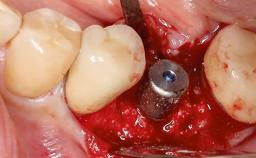

Treatment of Peri-Implantitis at a Zirconia Implant

Frank Schwarz, Ausra Ramanauskaite

Due to their promising clinical performance, zirconia implants have recently become popular alternatives to titanium implants, particularly for areas with high esthetic demands (Holländer and coworkers 2016; Roehling and coworkers 2016; Lorenz and coworkers 2019). However, regardless of the reported high survival and success rates, zirconia implants were affected by peri-implant diseases over the short observation period, suggesting the importance of treating peri-implant diseases at zirconia implants (Becker and coworkers 2017). In their case, Frank Schwarz and Ausra Ramanauskaite present 3-year results following mechanical debridement alongside Er:YAG laser monotherapy.